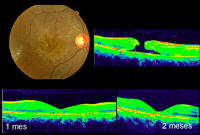

Figura 3. A) Varón joven con coroidorretinopatía serosa central aguda. B) Se aprecia un gran desprendimiento de la retina neurosensorial con afectación foveolar. En el corte tomográfico se muestra un desprendimiento localizado del epitelio pigmentario con la doble imagen epitelio pigmentario-membrana de Bruch y material hiporreflectivo entre ellas. C) La angiografía objetiva cómo el desprendimiento del epitelio coincide con el punto de fuga. D) Resolución espontánea del desprendimiento neurosensorial a los 2 meses.

Se hace imprescindible el seguimiento de las lesiones por OCT. Las formas agudas suelen presentar una evolución benigna en un 90% de los casos, por lo que es conveniente su control tomográfico. Diferentes autores aconsejan el control mediante agudeza visual y tomografía durante los primeros 3 meses, sin realizar tratamiento mientras se objetive una reducción en el grado de desprendimiento (

Figura 3D).